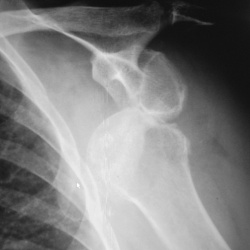

Травма. Пациент направлен на рентгенографию плечевого сустава.